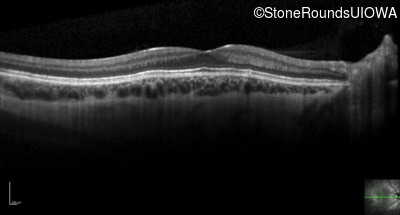

Optical Coherence Tomography - Right - 20/80 +2

Exemplar / OCT Stack

OCT Stack